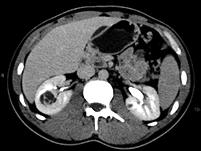

问题 男,45岁,右腰部隐痛不适伴无痛性肉眼血尿1个月,请结合图像,选择最可能诊断 ( )

选项 A、右肾盂癌 B、右肾脓肿 C、右肾血管平滑肌脂肪瘤 D、右肾感染性囊肿 E、右肾癌

答案 E